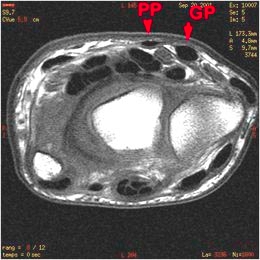

A à D : Coupes axiales du poignet de proximal en distal : Aspect normal du FRC (grand palmaire, fléchisseur radial du carpe) (GP) et du Petit palmaire. Rapports étroits de ces structures avec le nerf médian et les tendons fléchisseurs.

Aspect normal des tendons palmaires.